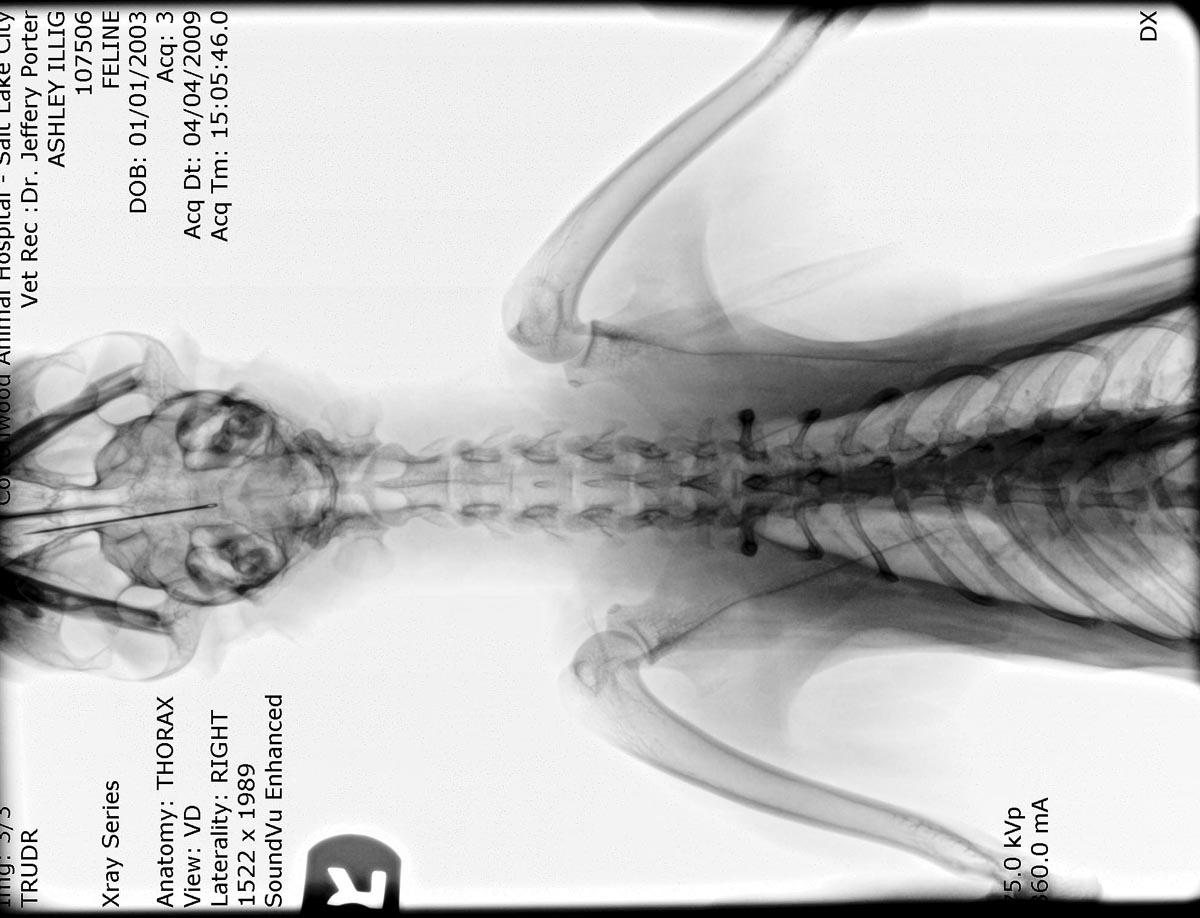

| Our second cat, Ashley tried to swallow a

needle.  Here is a negative of its X-ray. The needle is embedded in her palate. Click / tap the image to enlarge. |